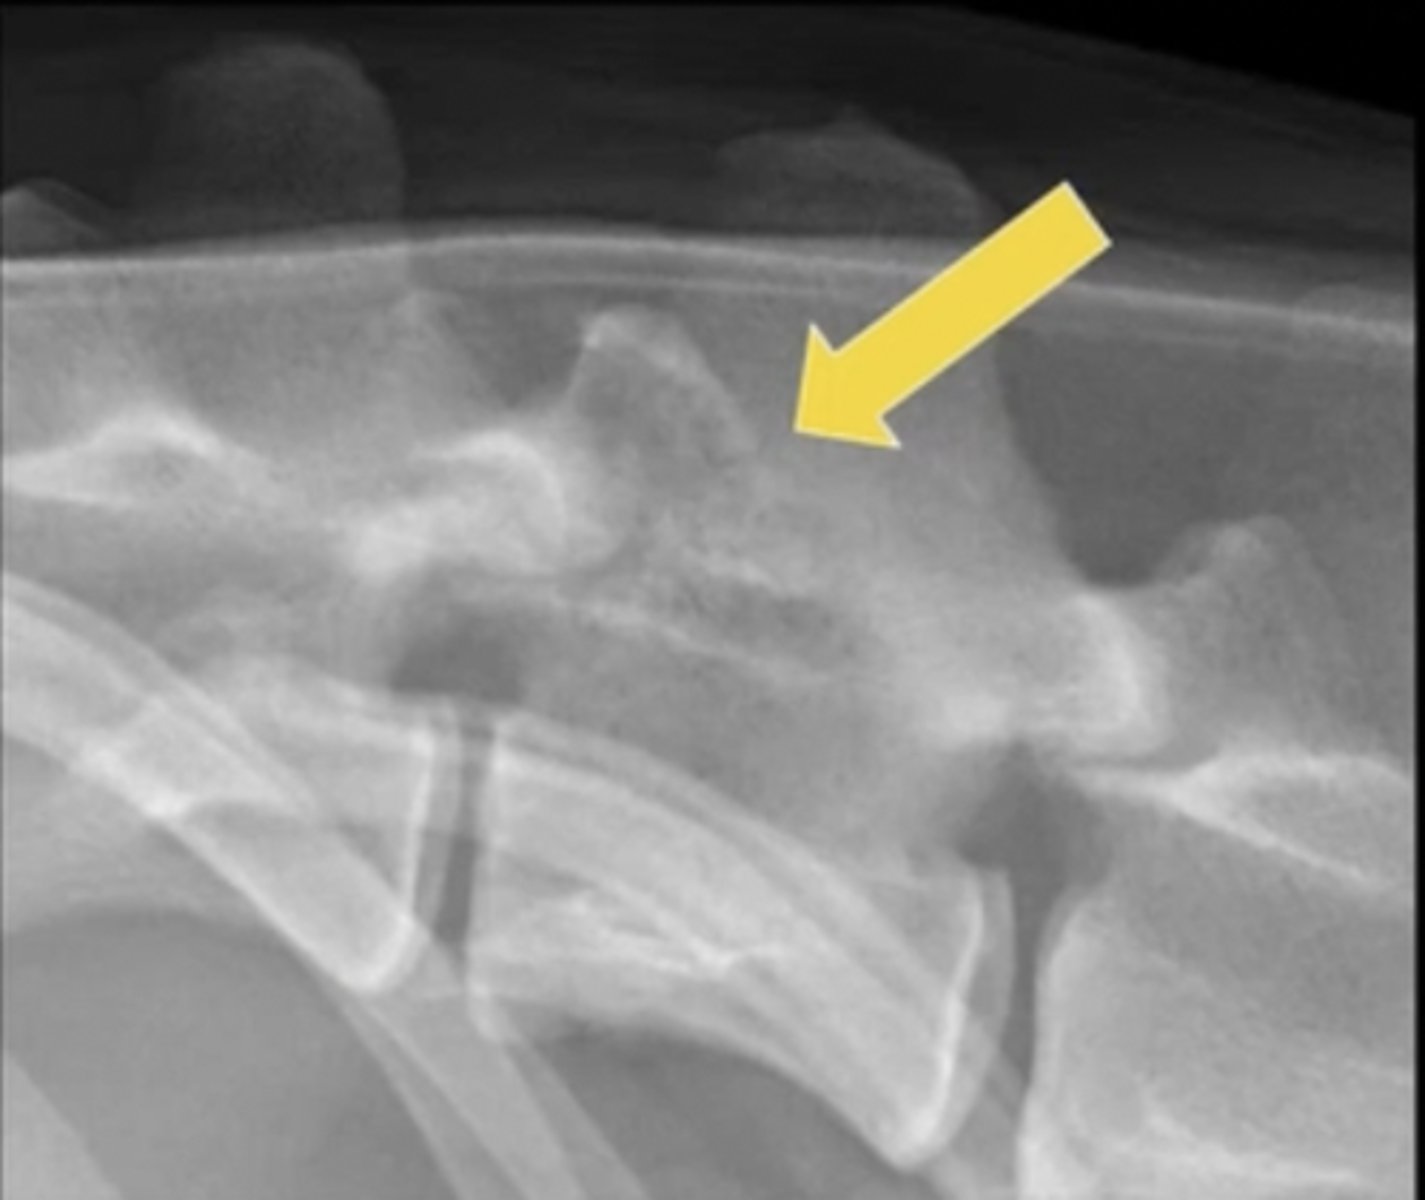

navicular flexor skyline view

What special equine view is this?